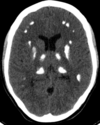

4

Q

A

Esclerose mesial temporal

Observe a perda de volume, que indica atrofia e causa aumento secundário do corno temporal do ventrículo lateral.

O sinal alto no hipocampo reflete a gliose.

How well did you know this?

Qual o padrão da Esclerose mesial temporal?

Atrofia hipocampal e hipersinal T2. Cerca de 10% dos casos são bilaterais (dificulta o diagnóstico). A etiologia é desconhecida, mas há uma relação entre STM e convulsões febris prolongadas no início da vida A esclerose mesial temporal pode ocorrer em associação com outras patologias, principalmente displasia cortical focal (dual pathology).